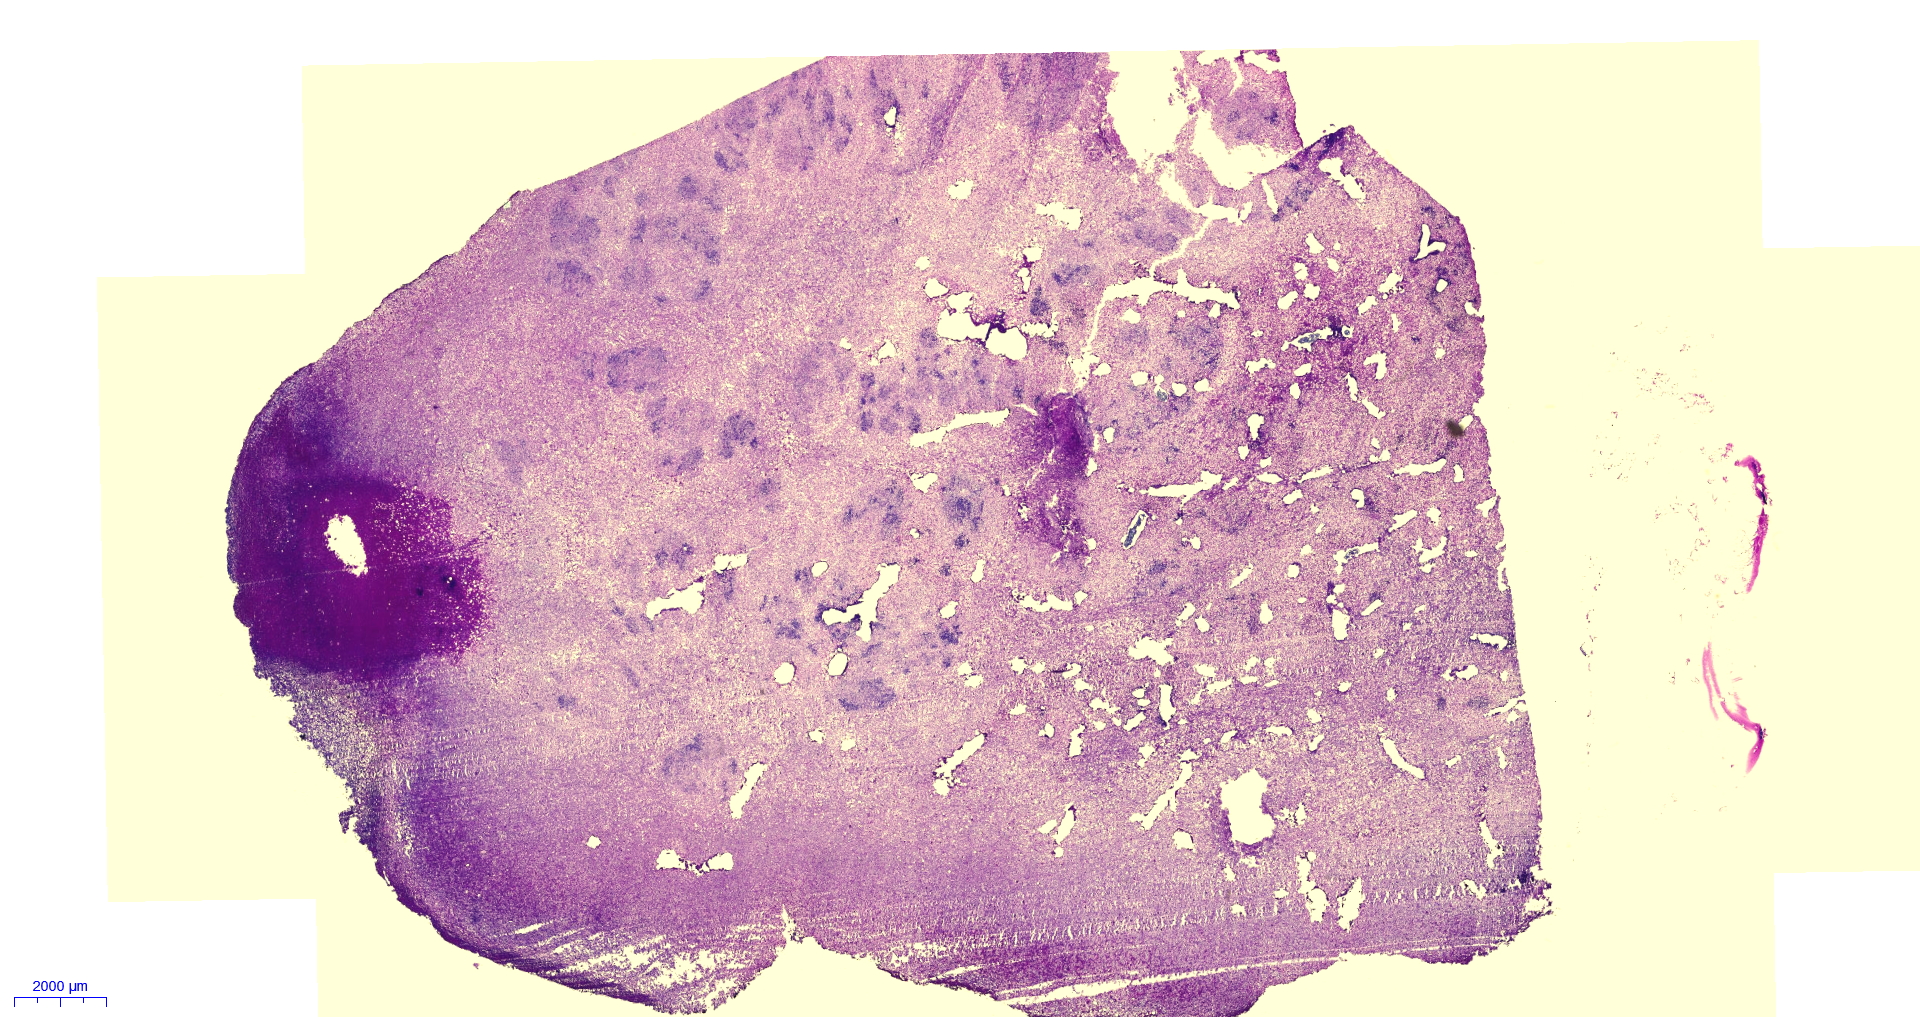

Das Material liegt mich seit knapp 2h vor und ich komme damit einfach nicht wirklich voran. Denn nicht nur das mir die passende Literatur dafür fehlt, viel schlimmer noch… Ich finde in keinem einzigen Präparat auch nur eine Spur von Sporen.

Morgen früh werde ich eine dünne Scheibe bei uns im Labor histologisch aufarbeiten… damit wir eine lichtdurchlässige Gesamtsicht erhalten ca. 1-3µm dick.